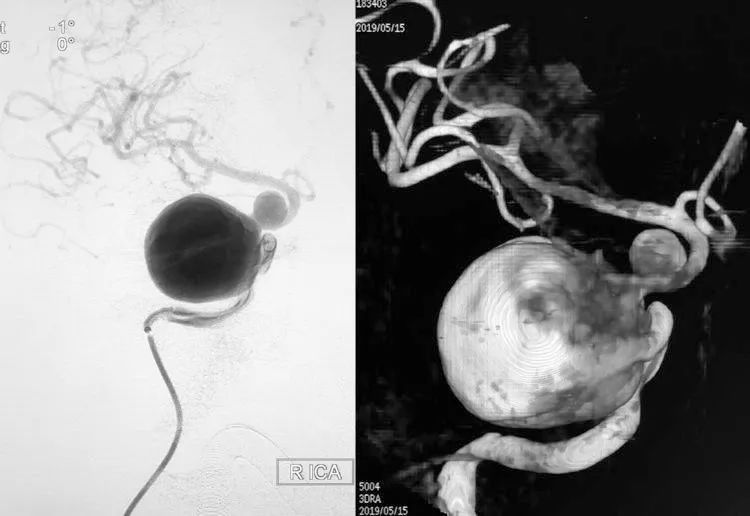

患者,女,51岁。因右眼胀痛不适1周入院,曾在门诊行脑MRI和MRA示颅内多发动脉瘤。

- 术前右颈内动脉造影显示右侧颈内动脉床突段巨大动脉瘤、床突上段中型动脉瘤。

- 巨大动脉瘤瘤体26.43 mm×26.77 mm,颈宽10.03 mm;中型动脉瘤瘤体8.26 mm×8.50 mm,颈宽5.75 mm。